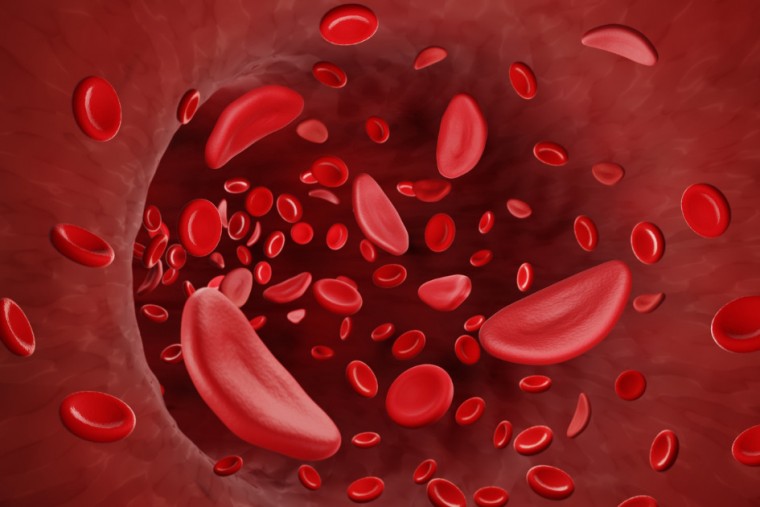

సికిల్ సెల్ వ్యాధిని ఎదుర్కోవడానికి ICMR, Zydus క్లినికల్ ట్రయల్ కోసం జతకట్టాయి

Publish : Mon, Oct 14, 2024, 08:02 PM